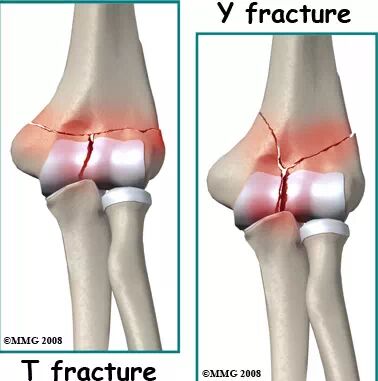

常見類型

伸直型:最多見,占85.4%,跌倒時肘部彎曲,手掌著地,地麵的反作用力經前臂傳導到肱骨髁上部致骨折發生;這類骨折不僅容易損傷橈(ráo)神經和正中神經,也容易導致肘內翻或外翻。

屈曲型:多由於間接暴力導致,跌倒時,肘部彎曲,肘後方著地,暴力傳導致肱骨下端導致骨折;由於肘後部皮膚薄弱,容骨折斷端易刺破皮膚,造成開放性骨折。

粉碎型:成年人多見,常見於車禍等暴力傷害。